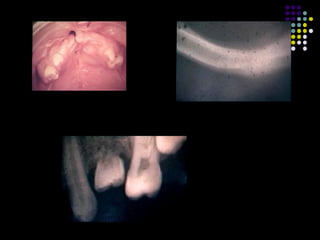

Odontodisplasia regional

 Involucra tejidos duros (esmalte, dentina, cemento).

 Los dientes se pueden afectar en una region, cuadrante o

mandibula.

 Presencia de raices cortas, foramen apical abierto y camaras

pulpares alargadas.

 Adelgazamiento y pobre mineralizacion del esmalte y dentina.

 Mayor afeccion de permanentes.

 Region anterosuperior mas afectada.

 Causa desconocida.

 Algunos factores asociados: traumas, deficiencias nutricionales,

infecciones, anormalidades geneticas, enfermedades sistemicas,

anormalidades metabolicas.

 Tratamiento: remocion del diente afectado.

Odontodisplasia